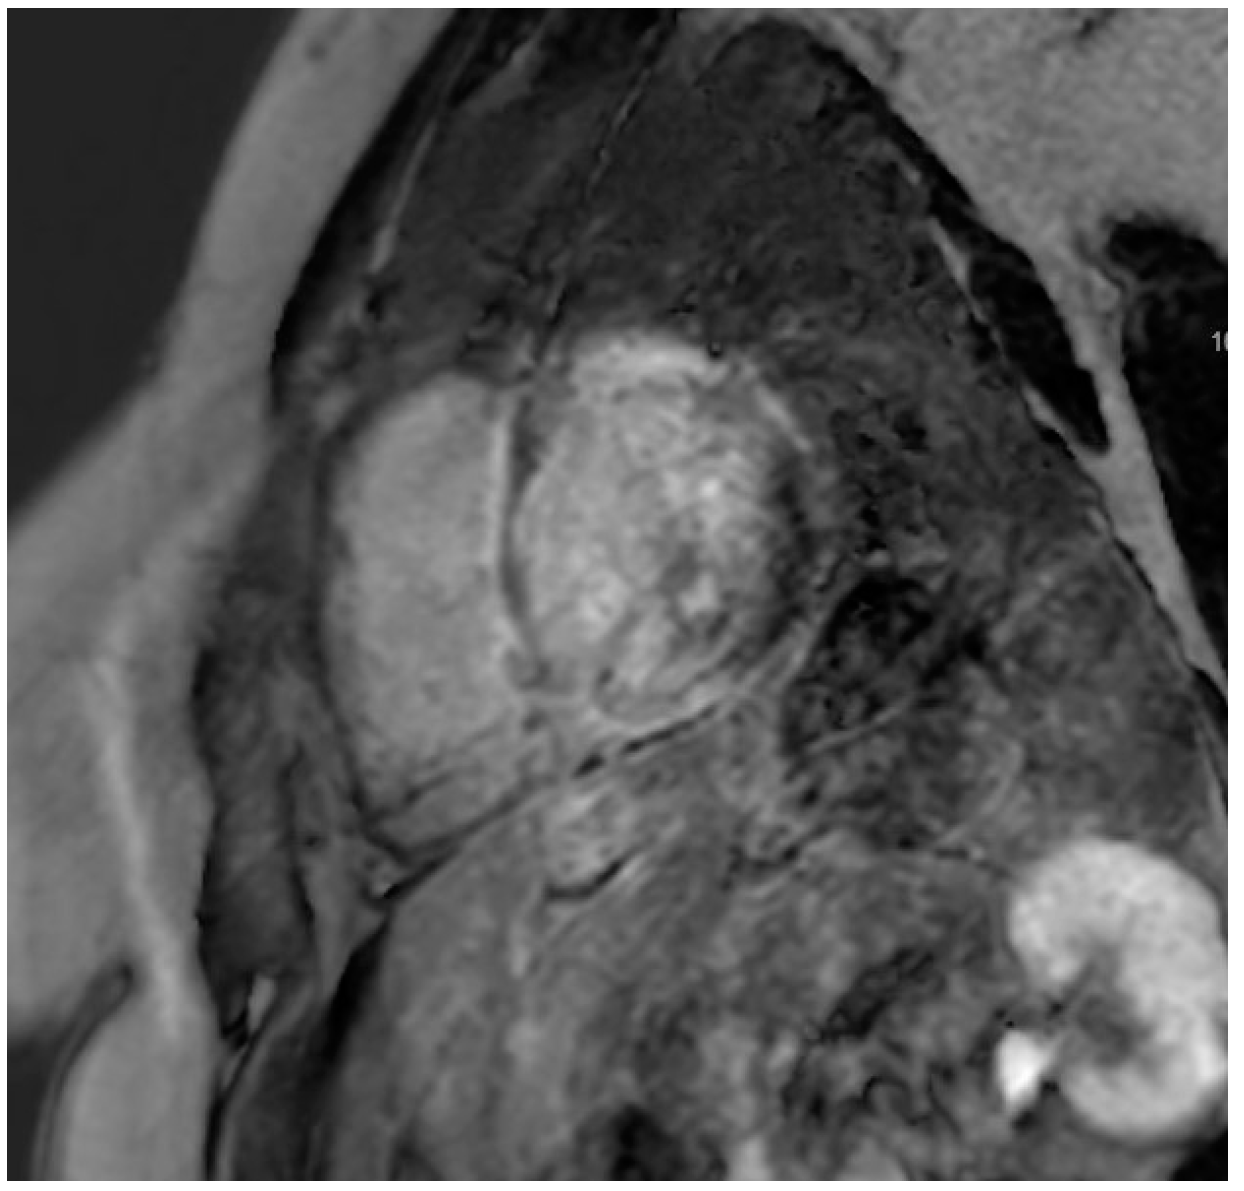

The protocol for PET/CT imaging necessitates a low-carbohydrate, high-fat diet prior to imaging studies to induce ketosis, thereby facilitating adequate physiological suppression of glucose uptake in the myocardium. While adherence to the dietary protocol was strongly encouraged, data on compliance were not recorded. Nonetheless, only participants who demonstrated adequate suppression, as indicated by their pre-imaging beta-hydroxy butyrate levels, were included in this study. Resting perfusion scans were obtained, after which patients received an injection of FDG, and subsequent scans were conducted 60 to 90 min post-injection. Segment-specific FDG uptake was documented using the American Heart Association (AHA) standardized 17-segment model, with the intensity of uptake quantified through standardized uptake values (SUV) [12,13]. The scans were evaluated for perfusion defects on resting scans, areas of FDG uptake after injection with FDG, and, in particular, “mismatch patterns” of FDG uptake corresponding to identified areas of perfusion deficit [12,14], which can be seen in Figure 1. CMR was performed in accordance with standard protocols, including late gadolinium enhancement (LGE), to assess for edema and fibrosis.

3.3. CMR Findings

Figure 3. CMR demonstrating LGE localized to the basal regions.